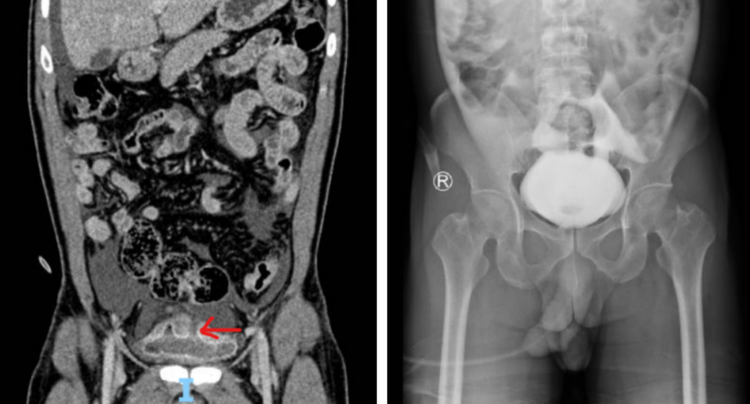

Chụp CT bụng và X-quang bàng quang cho thấy tình trạng dịch tự do trong phúc mạc và vỡ bàng quang. Ảnh: BVCC

Nhận định đây là trường hợp cấp cứu ngoại khoa nguy hiểm, ê-kíp phẫu thuật Khoa Ngoại niệu - Ghép thận - Nam khoa tiến hành mổ khâu phục hồi bàng quang hai lớp, đặt dẫn lưu ổ bụng và đặt sonde tiểu lưu. Về chấn thương gan độ I, ê-kíp Ngoại Tổng hợp quyết định điều trị bảo tồn thay vì can thiệp phẫu thuật.